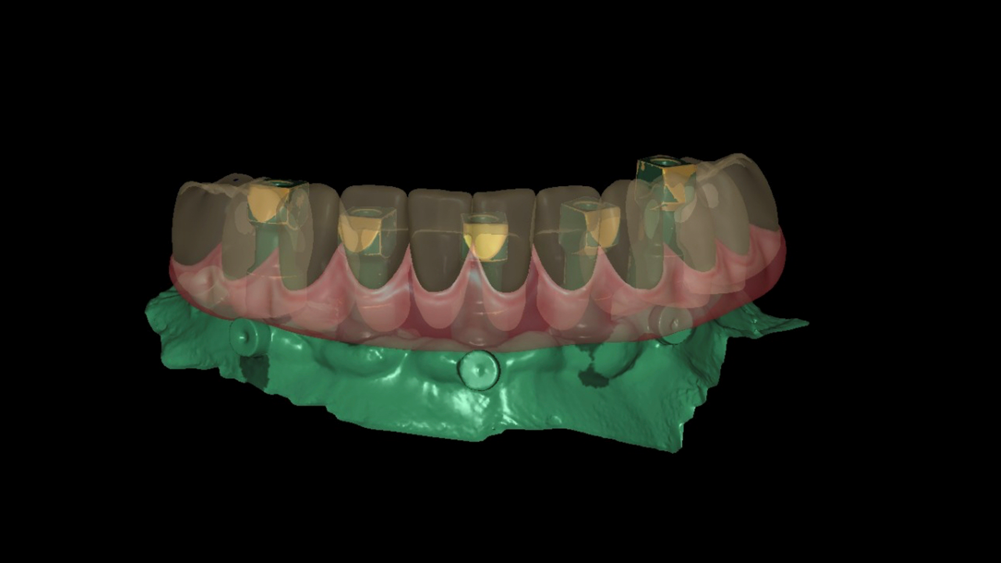

Uma vez alinhados os arquivos digitais, realize o desenho digital da prótese definitiva a partir da referência da prótese provisória (Figura 8).